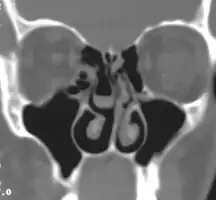

Bilateral concha bullosa, larger on the left -